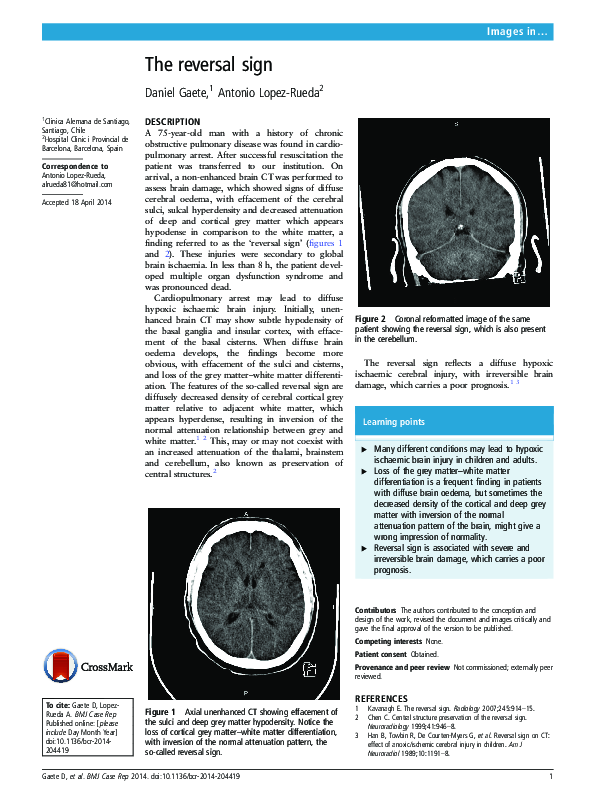

(PDF) The reversal sign